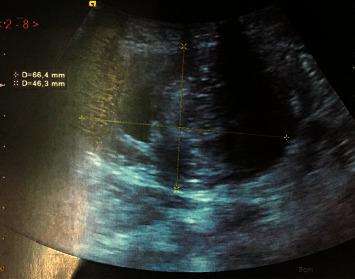

Acute intestinal invagination is the pathology of infants and small children. Its occurrence in adults is rare, and it represents 1 to 5% of intestinal occlusions often leading to the discovery of an organic cause that may be tumor. We report the case of a 72-year-old patient admitted to the emergency room of Ibn Sina Rabat, Morocco, for intestinal occlusion. The abdominal CT scan showed a voluminous intestinal invagination on a very probable heterogeneous digestive mass. The treatment was an open right hemicolectomy. The histopathological examination of the surgical specimen concluded a colonic well-differentiated adenocarcinoma with a 30% mucinous component. By review of literature, we discuss diagnostic and therapeutic procedures in emergency.